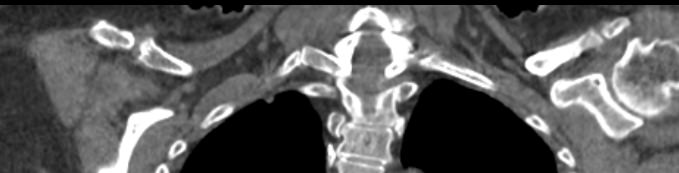

Наиболее информативным методом диагностики заболеваний ключицы является мультиспиральная компьютерная томография, которая наиболее часто применяется в ортопедии и травматологии. Метод основан на сканировании костей, суставов и внутренних органов при помощи веерообразного пучка рентгеновских лучей.

Источник рентгеновского излучения совершает непрерывное вращение вокруг объекта исследования и производит одномоментно множество послойных снимков, которые затем при помощи цифровой обработки данных преобразуются в трехмерные пространственные модели исследуемого органа.

В наших диагностических центрах обследование ключицы проводится на современном оборудовании экспертного класса. В клинике установлены новейшие мультиспиральные компьютерные томографы последнего поколения TOSHIBA AQUILION. Аппараты выполняют послойное сканирование исследуемой зоны с шагом от 0,5 мм, получая детальные снимки и трехмерные изображения высокого качества. При этом возможности аппаратов обеспечивают пониженный уровень лучевой нагрузки на пациента.